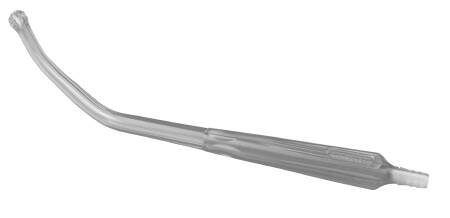

Conmed Suction Tube Handle Yankauer Style Non-Vented

| Application | Suction Tube Handle |

| Style | Yankauer Style |

| Tip Type | Bulb Tip Type |

| Type | Angled Type |

| Vent Type | Non-vented |

- Large lumen providing rapid aspiration

- Sturdy shatter-resistant construction enabling use for retraction

- Transparency allowing for clear visualization of fluids

- Side eyes to reduce traumatic tissue grab

- Includes pre-attached tube